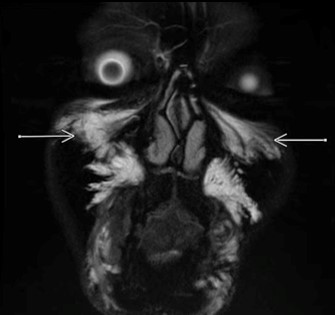

这是一位大约已经打了玻尿酸1-2年的朋友的MRI图像(这图着实有点吓人)

图中箭头指向的白 {MOD}部分就是玻尿酸了,这些玻尿酸旁边的黑 {MOD}区域就是脂肪。

图中,上面箭头指向的是玻尿酸,下面箭头指向的是脂肪。

还有就是由此可见,打玻尿酸一定要保守,别总觉得效果没了,就去打一次又一次,打苹果肌的各位,你们想变成花栗鼠吗??想变成大脸怪吗??

如果你曾经打过玻尿酸,那证明你脸上的浮肿不一定是脂肪造成的(你是真的肿了,不是胖了)。